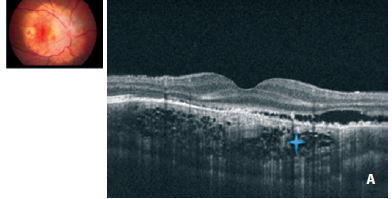

We observed a cage-like reflective pattern with the EDI OCT, which corresponds to the calcified region of the choroidal osteoma (Figure 2A). In some regions, a hyper-reflective band was visible between the calcified tumor tissue and unaffected choroid (Figure 3). The retinal tissue covering the calcified areas seemed intact (Figure 2, 3). FAF imaging of the calcified areas showed slight hyperautofluorescence indicating the integrity of RPE (Figure 1B).

We described three different reflectivity patterns in the decalcified area. First one was a thick hump-like hyper-reflective band, which had posterior acoustic shadowing and had a non-intact RPE overlying it (Choroidal neovascular membrane - CNVM) (Figure 2B). The outer retinal structures (RPE, IS-OS line and external limiting membrane) of the second pattern were disintegrated, the tumor plane was irregular and the vascular structures of the tumor were visible. In addition, the second pattern showed less acoustic shadowing compared to the first one. The third pattern was an irregular hyper-reflective pattern partially beneath or over the RPE and Bruch membrane. In FAF imaging, decalcified areas were mostly hypoautofluorescent although showed hyperautofluorescence in some parts (Figure 1C).

Choroidal thickness was increased in the RE, which had choroidal neovascularization. In addition, intra and subretinal serous fluid was observed. Outer segment elongations similar to the ones in central serous chorioretinopathy (CSCR) were evident. Hyperautofluorescence spots were evident in FAF imaging which correspond to the areas of serous fluid (Figure 1B).

In a previous histopathologic study, choroidal osteoma was demonstrated to be a tumor between the choriocapillaris and choroid, where the spongious dense bone trabeculae surround bone marrow with loose connective tissue and vessels(5). In this case, using the EDI OCT, we described a lattice-like reflective pattern that corresponds to the spongy bone in the choroid. Eduardo et al. have described a similar pattern in their study previously(6). The hyper-reflective line between the tumor and choroid in this study may be explained by the interface in-between or the choroidal melanocytes pushed towards the sclera by the tumor as described by Williams et al(5).

Time domain OCT and tomodensitometry (TD) (TD OCT) may reveal retinal disorders in cross sectional analysis but is able to show only a trace amount of choroidal details. TD OCTs of 22 choroidal osteoma patients showed the relation between photoreceptor atrophy with tumor decalcification(7). SD OCT has many advantages over TD OCT in means of high scanning rate and resolution. We have observed a similar correlation between photoreceptor atrophy with tumor decalcification. Atrophy of the RPE, serous retinal detachment and defects in outer segment of photoreceptor layer were observed in the decalcified area. The yellow-white region in the tumor was defined as decalcification. The yellow-white color is probably due to the degeneration of the orange RPE with tumor decalcification(1). Based on that, we may state that tumor decalcification is directly related to RPE atrophy. In addition, defects in Bruch membrane and RPE may contribute to CNVM formation and subsequently, serous retinal detachment. We defined CNVM as the hyper-reflective band between calcified and decalcified tumor, shadowing the structures beneath it.

Optical coherence tomography shows total disintegration of RPE in the area of serous detachment and elongation of outer segments. The decalcified areas were hypofluorescent due to the disintegration RPE configuration and function. We believe that the hyperfluorescence of focal points may be related to the remaining decalcified osteoma tissue, scleral collagen or metaplasia of the RPE. In addition, we also believe the granular hyperfluorescent area in the serous detachment area is related to outer segment elongations as described by Matsumoto et al. in cases with CSCR(8). In this case we were first to demonstrate the retinal vessels described by Gass et al. on the tumor surface beneath the retina with the EDI OCT(1).